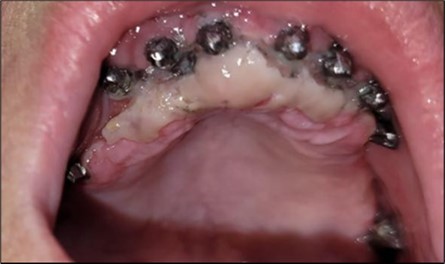

Figure 6.Definitive metal-ceramic prosthetic restoration cemented 4 days postoperatively: (a) Junction area at the mandible between the definitive metal-ceramic prosthetic restoration and the gingiva; (b) Junction area at the maxilla

Definitive metal-ceramic prosthetic restoration cemented 4 days postoperatively: (a) Junction area at the mandible between the definitive metal-ceramic prosthetic restoration and the gingiva; (b) Junction area at the maxilla